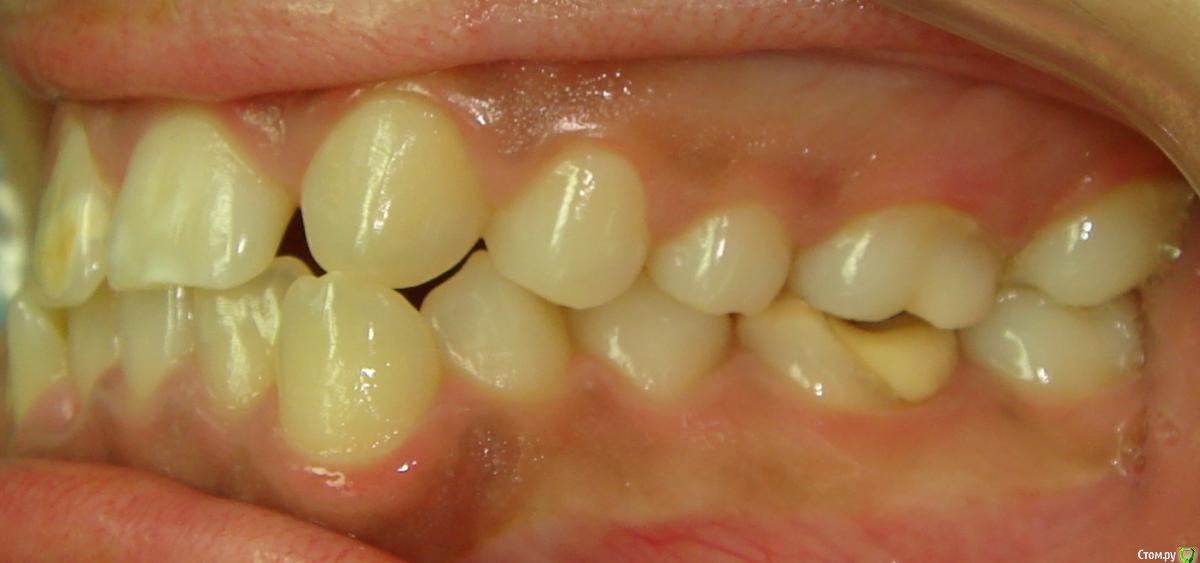

Opdihatop Опубликовано 20 февраля, 2017 Поделиться Опубликовано 20 февраля, 2017 Здравствуйте, коллеги! Вот такой вот случай третьего класса, вертикального роста, множественной первичной адентии и преинтереснейшего 13-го зуба. Девочке 14 лет. Сразу скажу, что вопреки некоторым классикам удалять клык или премоляры мы не будем, будем ставить в дугу, причем на его законное место. Может у кого-то были подобные случаи, поделитесь опытом, будьте добры. Какой план лечения и какая биомеханика тут будут самыми оптимальными? Заранее всем спасибо! Ссылка на комментарий

Opdihatop Опубликовано 20 февраля, 2017 Автор Поделиться Опубликовано 20 февраля, 2017 52, 53 молочные. 12, 22 - адентия. Клык пойдет на место 13. Когда-то на курсе Рафаэля Спены видел подобное, но, к сожалению не зафиксировал на фото. В общем и целом принцип помню. Но тут есть одно огромное НО... 14, 15 началась резорбция верхушек из-за 13 зуба, что видно по КТ. Ссылка на комментарий

Yana guapa Опубликовано 20 февраля, 2017 Поделиться Опубликовано 20 февраля, 2017 у ВАшей девочки я бы удаляла восьмерки, ставила винты в подскуловую область , часть зубов назад, а часть - пружинами вперед. создавая место. про клык - здесь конечно по КТ надо смотреть, куда его тащить и как открывать. Возможно лучше вначале открыть место (раздвинуть 5ку и 4ку) а потом клык поставить между ними. Клык станет 4кой а 4ка клыком. (имхо) 1 Ссылка на комментарий

Opdihatop Опубликовано 20 февраля, 2017 Автор Поделиться Опубликовано 20 февраля, 2017 (изменено) вот такая штучка еще в кости... Видел, на вид - простая остеомка, так что пугать пациента не буду, передвижению зубов не мешает. а про каких именно классиков Вы говорите? (это я для себя, для развития..) Вот простите, не вспомню, читал монографию какого-то итальянца еще на этапе обучения, так там было сказано вообще их удалять, особенно при транспозиции через ц.л. у ВАшей девочки я бы удаляла восьмерки, ставила винты в подскуловую область , часть зубов назад, а часть - пружинами вперед. создавая место. про клык - здесь конечно по КТ надо смотреть, куда его тащить и как открывать. Возможно лучше вначале открыть место (раздвинуть 5ку и 4ку) а потом клык поставить между ними. Клык станет 4кой а 4ка клыком. (имхо) Подскуловые импланты, это классно, только вот в Украине этих корейцев не продают пока (Диаметра не хватает и длины). Дистализирую пружинами при непрямом анкораже на микроимплантате между 5 и 6. Как я собирался тянуть клык вперед? На 14, 15 ставятся брекеты от нижних премоляров и ставятся они на толстую композитную подушку, которая постепенно утолщается. Таким образом зубы постепенно уходят орально, а их корням придается небный торк, освобождая путь в кости для 13. Затем при помощи компактостеотомии быстро мезиализируется 13, затем 14 и 15 плавно перемещаются назад (хотя 15 это вряд ли коснется... его я планирую перед этим дистализировать). Сам я такое не делал, но видел на курсе. Вот, выпал шанс попробовать. Зачем? Во-первых, научный интерес, во-вторых, родители категорически против ремоделирования коронок зубов... Изменено 20 февраля, 2017 пользователем Opdihatop Ссылка на комментарий